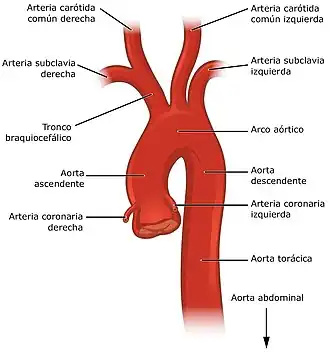

Aorta ascendente

Es la primera porción de la aorta, mide unos cinco centímetros de largo, parte del ventrículo izquierdo del corazón con quien se comunica a través de la válvula aórtica. Nada más salir se inclina hacia delante y la derecha, pasando por delante de la arteria pulmonar, en su mismo origen da las dos primeras ramas, la arteria coronaria izquierda y derecha que son de importancia crucial, pues abastecen de oxígeno y nutrientes al corazón.[7][8] Presenta una dilatación en su inicio denominada bulbo de la aorta, que corresponde a la visualización exterior de los senos aórticos (o de Valsalva), de los que se originan las arterias coronarias.

Arco aórtico

El arco aórtico, también llamado cayado aórtico, se encuentra entre la aorta ascendente y descendente. Su porción central o proximal tiene forma de u invertida y da origen al tronco braquiocefálico, la carótida común izquierda y la subclavia izquierda. En el punto medio de este arco o cayado la aorta pasa desde el mediastino anterior al mediastino posterior. En la pared del arco aórtico se localizan gran cantidad de terminales nerviosas sensibles a la presión que reciben el nombre de barorreceptores y son de gran importancia para el mantenimiento de la presión arterial. Muy cerca se encuentran los cuerpos aórticos que son grupos de células que forman pequeñas estructuras de alrededor de 2 mm de diámetro que contienen quimiorreceptores capaces de detectar los cambios en la composición de la sangre, sobre todo la concentración de oxígeno.[9]

La aorta ascendente emite dos ramas, las arterias coronarias, que distribuyen sangre en el miocardio. Luego, gira hacia el lado izquierdo del cuerpo, donde forma el cayado de la aorta (arco aórtico), el cual desciende y termina a nivel del disco intervertebral que separa la cuarta y la quinta vértebra dorsal.

- Ramas de la porción ascendente: arterias coronarias.

- Ramas del cayado de la aorta (arco aórtico): tronco braquiocefálico, arteria carótida común izquierda y arteria subclavia izquierda.